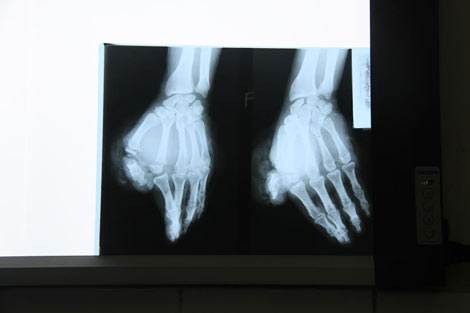

| Hình ảnh trước và sau ca phẩu thuật của bệnh nhân Thành. |

Trước đó, ngày 18/8, trong lúc sử dụng máy cưa để làm mộc, anh Thành không may đã bị máy cắt đứt lìa ngón tay trỏ và ngón tay cái. Ngay sau khi bị nạn, anh Thành đã được người nhà khẩn trương đưa vào Bệnh viện Đa khoa huyện Thanh Chương sơ cứu rồi chuyển xuống Bệnh viện chấn thương chỉnh hình Nghệ An.

Tại đây, bệnh nhân đã được các bác sỹ cấp cứu kịp thời, sau đó tiến hành phẫu thuật nối chi bằng phương pháp hiện đại. Sau một thời gian ngắn, bệnh nhân Thành đã hồi phục sức khỏe, tỉnh táo, 2 ngón tay đã có dấu hiệu sống. Đây là bệnh nhân thứ 2 bị đứt lìa chi được Bệnh viện chấn thương chỉnh hình nối thành công bằng kỹ thuật nối chi.